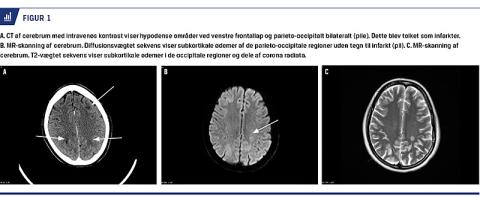

Fem timer senere udviklede patienten blindhed og hovedpine og fremstod konfus. Man påbegyndte behandling med MgSO4. To timer efter symptomdebut foretog man i generel anæstesi et ukompliceret sectio med fødsel af et rask barn, efter stabilisering af et blodtryk på 180/110 mmHg. En postoperativ CT af cerebrum viste infarkter og gav mistanke om sinustrombose (Figur 1A). Patienten blev overflyttet til et tertiært center under fortsat sedation med henblik på MR-skanning. Denne afkræftede sinustrombose, men bekræftede cerebralt ødem, hvilket tydede på PRES (Figur 1B og C). Patienten havde ingen synsudfald, da hun vågnede. MgSO4 blev seponeret efter 24 timer, og man påbegyndte behandling med tablet labetalol og nifedipin. Ved udskrivelse efter 16 dage havde patienten let hukommelses- og koncentrationsbesvær.